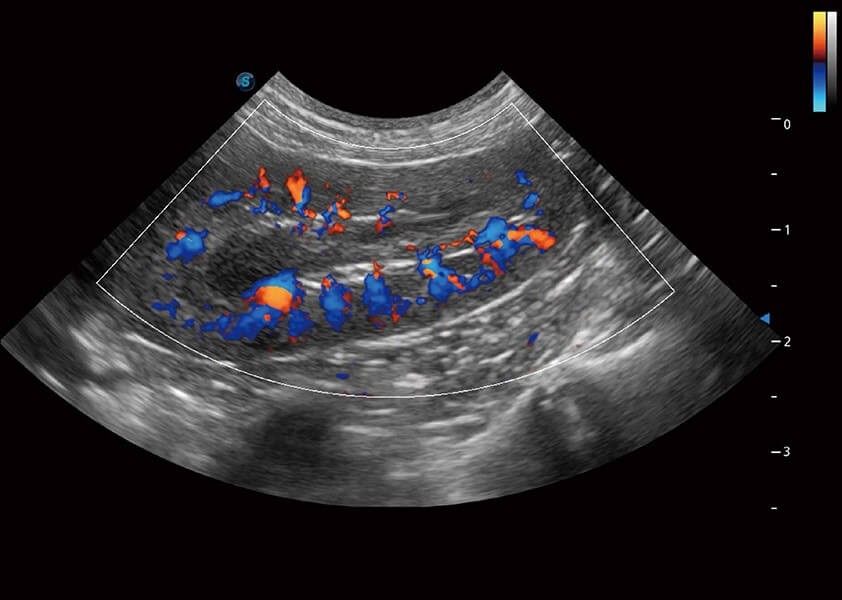

ProPet 60 作為一款高端臺(tái)式動(dòng)物超聲設(shè)備,為動(dòng)物醫(yī)生的日常診斷提供了一系列貼合動(dòng)物臨床需求、解決臨床實(shí)際問題的高級(jí)成像功能。憑借全系列高清探頭,滿足醫(yī)生對(duì)腹部、心臟、生殖、淺表、肌骨等成像的所有需求,切實(shí)幫助您提升檢查效率,提高診斷信心。